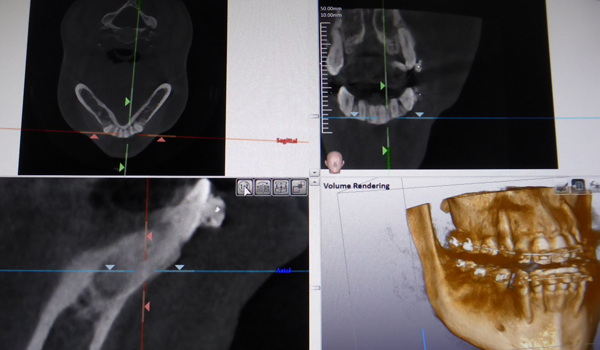

矯正治療

元の歯並びによって違いますが 歯を大きく動かすと歯茎がやせてしまうことがあります。

矯正を開始する前に歯の周りの骨の量を確認し、矯正後に歯茎の退縮量を減らすための矯正方法を選択するためにCTを使用します。

歯周病治療

CTを撮影することで、骨の状況を正確に確認できます。

現在、様々な方法で骨の再生が可能となってきております。 再生療法の成功率を高めるためにCTは重要な役割を果たします。